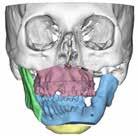

A la exploración (Figura 4 pre-quirúrgicas), observamos una facies birre trusa sobre todo a expensas de una severa retrusión mandibular, con una gran asimetría facial, con una evidente desviación del mentón a la izquier da, un canteo maxilar derecho, una asimetría de líneas medias faciales, una apertura oral de 15 mm (normal >40 mm), ausencia de palpación de cóndilo izquierdo, un edentulismo parcial fundamentalmente de sectores posterio res izquierdos y una maloclusión clase II división I.

Para completar el estudio, se solicitó una tomografía axial computoriza da craneofacial (TAC) (Figura 1), dónde tras un examen exhaustivo a través de distintos cortes y reconstrucción 3D, evidenciamos una anquilosis de la ATM a la base de cráneo, desapareciendo por completo la anatomía nor mal de la ATM y su relación habitual con las distintas estructuras neurovas culares, así como la gran deformidad esquelética resultante del crecimiento y desarrollo craneofacial anormal.

Una vez los dientes fueron colocados mediante ortodoncia en el lugar estratégico en la arcada, se realizó una planificación quirúrgica 3D de los movimientos quirúrgicos de los maxilares en colaboración con la empresa americana encargada de la confección de la prótesis. Se diseñaron así unas guías quirúrgicas para la resección del bloque anquilótico, unas guías qui rúrgicas para la realización de la mentoplastia y el diseño de la prótesis individualizada y personalizada (Figura 2).

Gracias a esta planificación, se logró una mayor precisión en los movi mientos quirúrgicos, una mayor predictibilidad y reproducción, una dismi nución de los riesgos quirúrgicos por mediciones de estructuras anatómicas concretas (como la arteria carótida interna, el nervio facial, el nervio man dibular, la arteria maxilar interna…) (Figura 1) y un menor tiempo operato rio, entre otras ventajas.

Tras la planificación, se imprimió el esqueleto craneofacial en forma de modelo esterolitográfico en 3D (Figura 2A), para de manera intraoperato ria poder corroborar la localización quirúrgica, al ser una cirugía con una enorme dificultad de orientación tridimensional (Figura 2B).

Figura 1. Diagnóstico prequirúrgico del bloque anquilótico. Imágenes TAC en 3D, corte axial y corte sagital..